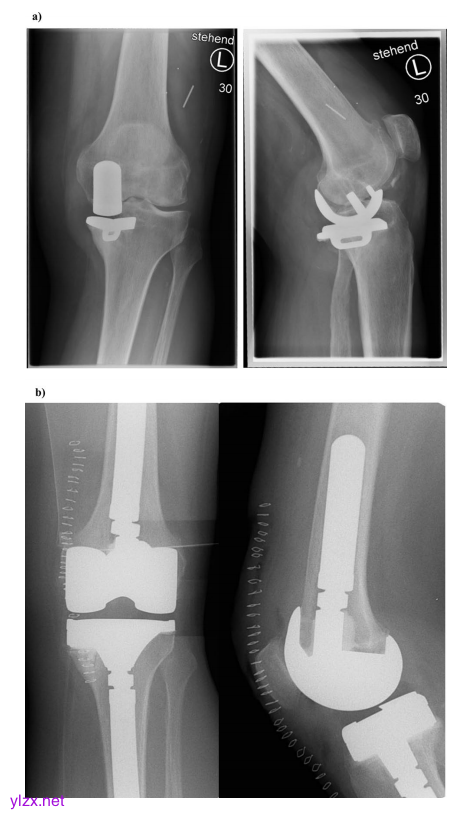

病例1显示了一名71岁的女性患者,其内侧半假肢松动,胫骨连续出现骨性KDC 2缺陷和内侧不稳定KDC B。可以看到一个旋转不良的半假肢松动。临床上,患者还表现出内侧不稳定,极有可能发生骨和韧带损伤(KDC B)。b术后x射线左前后视图和右侧视图。胫骨KDC 2骨缺损已通过块体增强(10 mm)进行治疗,除了模块化非骨水泥股骨干假体外,还产生了足够的力传递和旋转稳定性。由于关节线解剖重建后仍不稳定,选择了半约束植入物